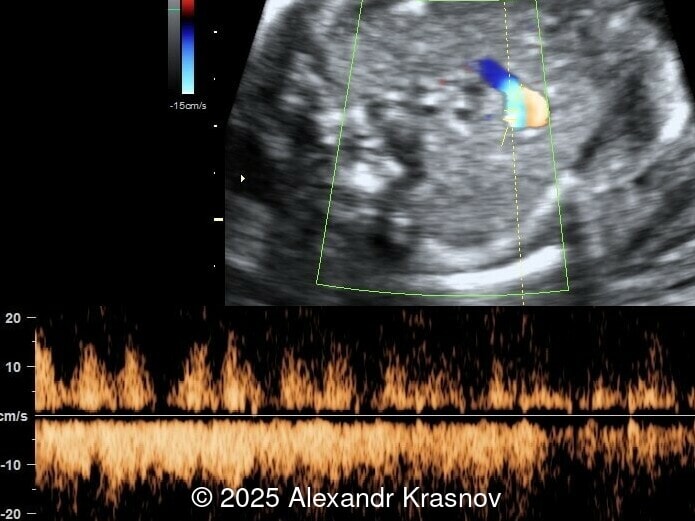

Our ultrasound showed biometry data corresponding to 21 weeks of gestation. During echocardiography, an abnormal drainage of the pulmonary veins was detected in which the pulmonary veins drain into a venous collector linked to the superior vena cava. The four-chamber view and the three-vessel view were altered and raised suspicion of a pathology. The grayscale and color Doppler images of the four-chamber view indicate a smooth posterior wall of the left atrium, increased distance between the left atrium and the descending aorta and the absence of pulmonary veins entering the left atrium (Image 1, 2; Video 1, 2). In the three-vessel view, the diameter of the superior vena cava appears larger than that of the aorta (Image 3, Video 3). In the images of the venae cava, a significant difference is seen between the diameters of the inferior and superior vena cava with significant enlargement of the superior vena cava (Image 4, Video 4). Additionally, there is a pulmonary venous confluent chamber (“twig sign”) behind the left atrium (Image and Video 5). A vertical ascending vein connects the confluent chamber with the superior vena cava where it drains blood from the pulmonary veins (Images 6, 7; Video 6).

In many cases, direct signs are not visualized, thus identification of indirect signs allow us to suspect this pathology, not diagnose it. They are based on morphological findings such as increased post‑left atrium space, or on hemodynamic changes such as ventricular disproportion, dilated superior vena cava or coronary sinus, and abnormal Doppler waveforms. The presence of a pulmonary venous confluence leads to an increased distance between the left atrium (LA) and the descending aorta (DAo) [9]. While visualization of the confluent chamber may be difficult, objectively measuring the increase in the space behind the left atrium in an axial section may be easier to verify. Various indices have been proposed for this purpose, the most widely used being the “post‑LA space index” described by Kawazu et al [10]. It is calculated as the ratio of the LA‑DAo distance to the diameter of the DAo, proposing a value ≥1.27 as a potential marker of TAPVR. In clinical practice, a cut-off of 1.0 may be more useful to increase detection rates, although this would be at the expense of more false positives. An alternative marker with a similar diagnostic performance and independent of the gestational age is the “left atrial posterior space to diagonal ratio,” which is calculated by dividing the LA‑DAo distance by the left atrial diameter, with an optimal cut-off ≥0.35 [11]. Asymmetric ventricular chamber dimensions with right heart dominance result from extra‑abnormal flow from the pulmonary veins to the right heart, providing a diagnostic clue for TAPVR [9], but this finding is late and not very specific. In supracardiac TAPVR, anomalous pulmonary venous drainage increases blood flow to the collector, which travels to the right atrium through the dilated innominate vein and superior vena cava, visible in the three-vessel trachea and bicaval views [7,12]. In the subcostal view of pediatric echocardiography, the cardiac type is characterized by the “whale’s tail sign,” where left and right pulmonary veins drain into the dilated coronary sinus. Although it is a technically difficult plane to obtain in fetal echocardiography, it has been described by Karmegaraj in a 25-week-old fetus [13]. Spectral Doppler waveforms are typically normal or biphasic in cardiac type, whereas in supracardiac and infracardiac types, the waveforms can be biphasic, monophasic, or continuous [6,7]. Color and spectral Doppler assessment allows the identification of the fetuses with pulmonary venous pathway obstruction and, therefore, at risk for acute postnatal deterioration with severe respiratory distress and cyanosis [14].